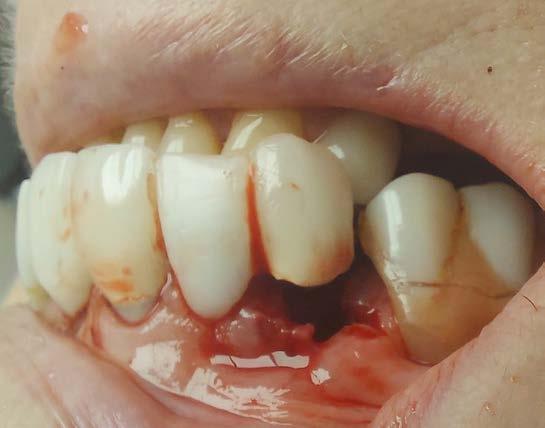

Cover: It’s a tricky situation. Patient with partial denture

Technique for extracting tooth or root tip from underneath fixed partial denture emphasizes use of magnification from dental loupes or dental surgical operating microscope for precision when performing technique-sensitive procedure. Case report.